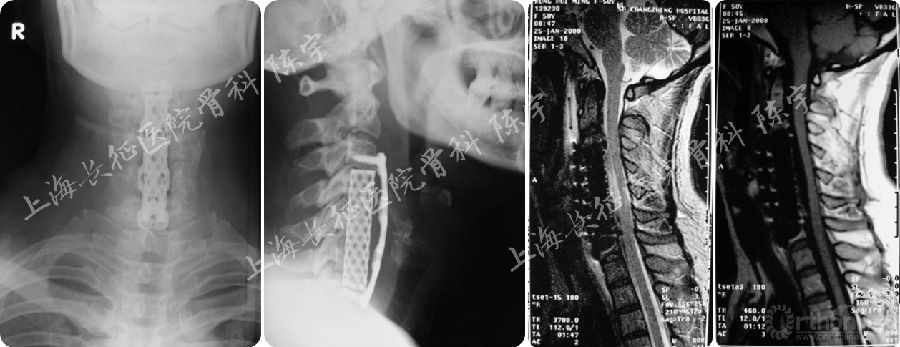

随访结果(5年):

随访第5年,患者神经功能完全恢复,JOA评分17分,颈前路钛网植骨融合,内固定位置良好,脊髓及硬膜囊形态进一步恢复,硬膜囊骨化进一步向前漂移并与前方植骨融合(图3A-G)。